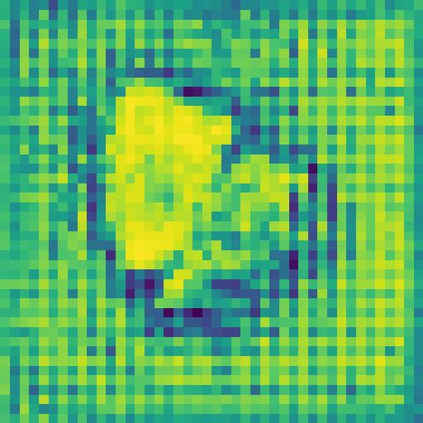

Skin lesion segmentation from dermoscopy images is of great significance in the quantitative analysis of skin cancers, which is yet challenging even for dermatologists due to the inherent issues, i.e., considerable size, shape and color variation, and ambiguous boundaries. Recent vision transformers have shown promising performance in handling the variation through global context modeling. Still, they have not thoroughly solved the problem of ambiguous boundaries as they ignore the complementary usage of the boundary knowledge and global contexts. In this paper, we propose a novel cross-scale boundary-aware transformer, \textbf{XBound-Former}, to simultaneously address the variation and boundary problems of skin lesion segmentation. XBound-Former is a purely attention-based network and catches boundary knowledge via three specially designed learners. We evaluate the model on two skin lesion datasets, ISIC-2016\&PH$^2$ and ISIC-2018, where our model consistently outperforms other convolution- and transformer-based models, especially on the boundary-wise metrics. We extensively verify the generalization ability of polyp lesion segmentation that has similar characteristics, and our model can also yield significant improvement compared to the latest models.